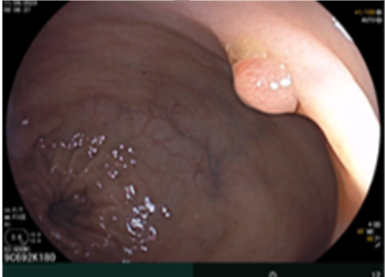

- Nội soi dạ dày, đại trực tràng: Polyp trực tràng kích thước 0,5cm

Hình 3: Hình ảnh polyp trực tràng kích thước 0,5cm

Đối với bệnh nhân này,  bệnh nhân đã được tầm soát nội soi đại trực tràng chỉ có 1 polyp kích thước 5mm và khai thác tiền sử gia đình không liên quan đến hội chứng đa polyp có tính chất gia đình, đánh giá sau mổ đã lấy hết tổn thương u, do đó bệnh nhân được chỉ định tiếp tục theo dõi định kỳ sau phẫu thuật bằng cắt lớp vi tính và nội soi đại trực tràng và các xét nghiệm thường quy khác.